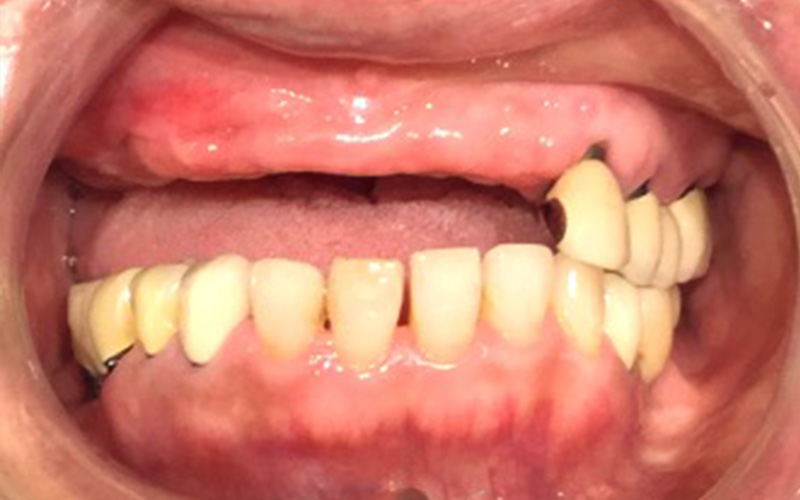

右側上顎洞にサイナスリフト処置を行い、同日にインプラント体を2本の埋入。2か月後に左右前歯部にインプラント体のを4本埋入。インプラントと骨が結合したのを確認後、仮歯の装着を行い、咬合の安定を図り、最終補綴処置をジルコニア性上部構造物にて作成を行い装着。

治療後の画像